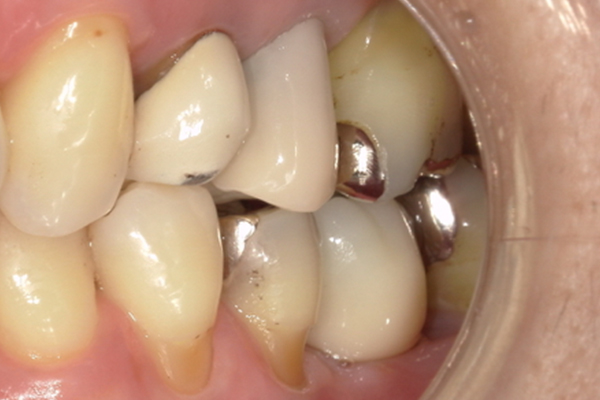

| 主訴 | 奥歯で噛めない、顎が痛い |

|---|---|

| 治療内容 | 奥歯のインプラント治療、前歯・奥歯の被せ物治療 |

| 治療期間 | 6ヶ月 |

| 治療費 | 350万円 |

| 治療リスク | 被せ物をつけた初期の段階で歯がしみることがある(時間とともに改善する) インプラント治療後に3日程度痛みと腫れを伴うことがある |